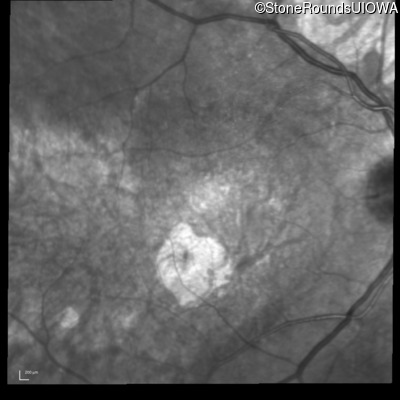

Infrared Fundus Photograph - Right - 20/125 -2

Exemplar